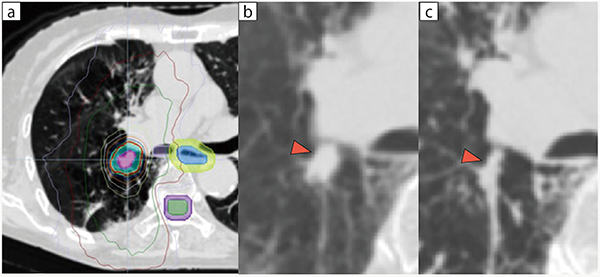

図4 動体追尾照射困難例

a:線量分布図,b:治療前のCT(▶腫瘍),c:照射期間中のCT(▶腫瘍)

腫瘍縮小(c▶)により,動体追尾照射の継続が困難であった。